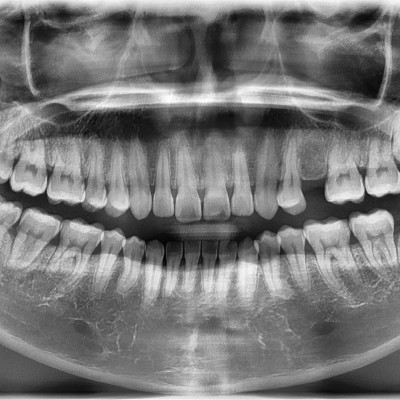

#18,28,38,48 사랑니 발치 #18,28,38,48 사랑니 발치 구강 외과 전문의가 당일 발치했습니다. --------------------..

작성자 이턱이 작성일 02-04 조회 1